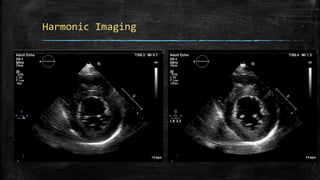

Harmonic Imaging

• When an ultrasound wave passes through the body, the

tissue generates "harmonic ultrasound waves" because

the tissue resonates.

• The resonance frequency is typically a multiple of the

original frequency (transmitted frequency)

• Fundamental components are filtered out.

• Images produced with harmonic imaging have a higher

resolution and are associated with fewer artifacts than

conventional (fundamental) imaging